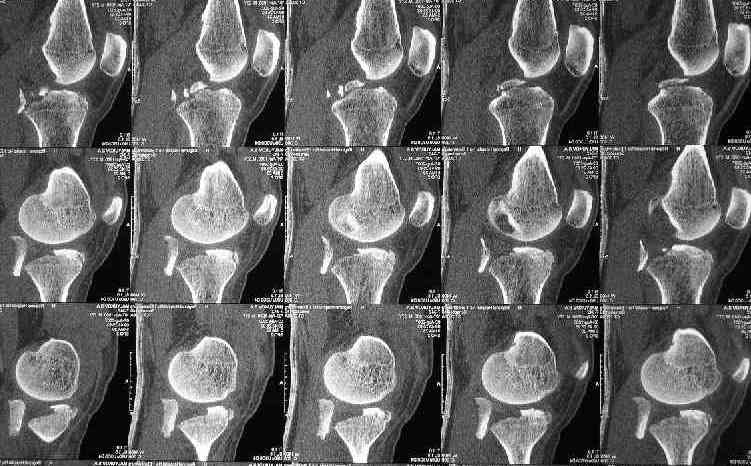

Based on the images ( it would be nice to have axial cuts),it seems to be posteromedial fragment, almost all the way into

posterior portion of the tibial eminance.

I thank for attaching the CT scan. it makes all the details very clear.

the approach should be standard posterior one (same that we use to fix the avulsed PCL).

the fragment is rotated and hence may require some manipulation, especially in flexion of the knee joint.

fixation may be with cancellous screw and washer.

Для определения доступа сагитальные срезы менее информативны, необходимо иметь корональные срезы.

Корональные срезы дают информацию об апексе перелома, и также информацию о вовлечения суставной поверхности, что является немаловажным для прогноза.

Операция из разряда травматологической "экзотики" прошла успешно. Доступ понравился:анатомичный, хорошая визуализация, удобно работать и оператору и ассистентам. Наложили пневможгут, но воспользовались им только на этапе ревизии сустава. Фрагмент развернулся на 90 град. на 2-ух "жгутах": медиально - сухожилие m.semitendinosus, латерально - задняя крестообразная связка. Мобилизовали,развернули и уложили на место без особого труда. Фиксировали отмоделированной 1/3-трубчатой пластиной. Мениск оказался неповрежден. Сустав стабилен. Обошлись без

иммобилизации, планируем начать ранние движения. Остальное на фото, дополнительно приложены корональные срезы КТ.